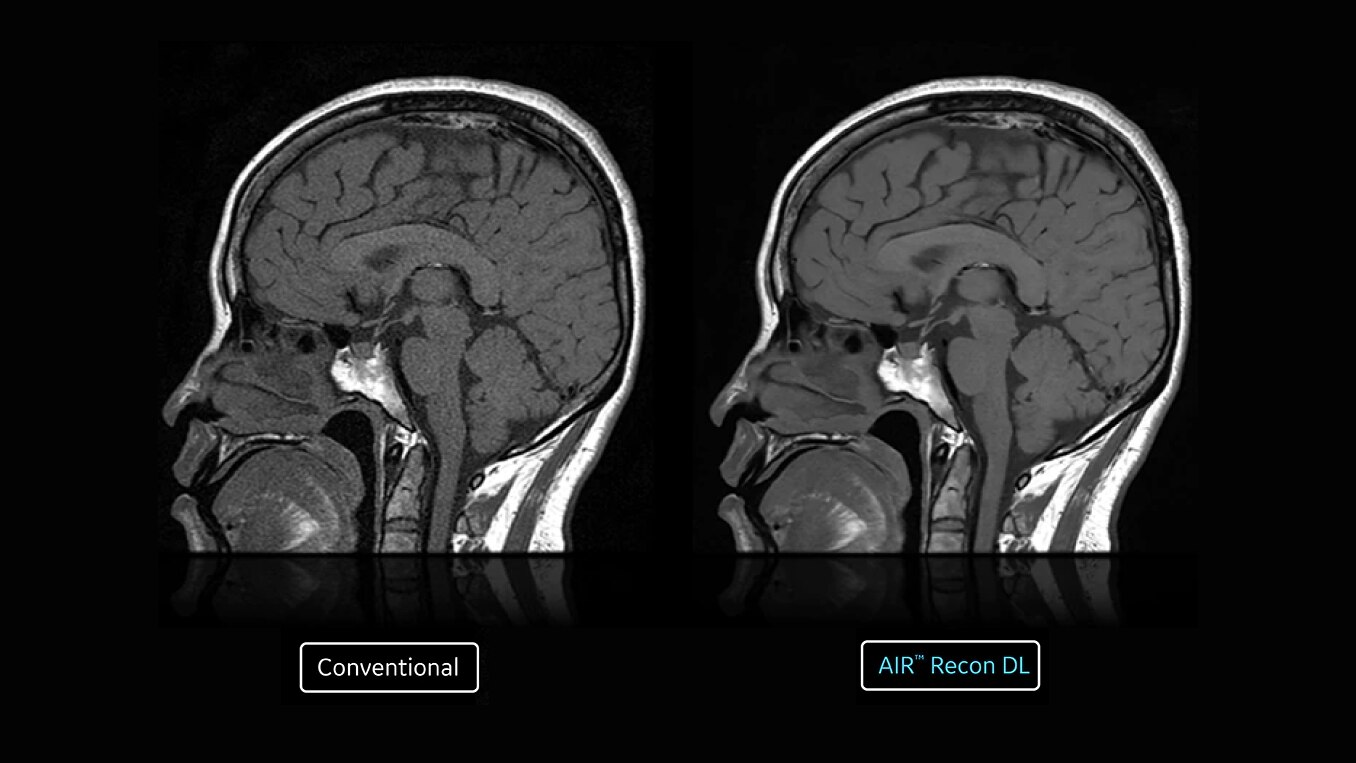

With SIGNA™ Prime, you don’t have to choose between accessibility and quality. We equipped SIGNA™ Prime with state-of the-art Total Digital Imaging (TDI) 2.0 technology. We paired that with the latest AI technology to generate images that are as easy to read as the system itself is to use. SIGNA™ Prime includes AIR™ Recon DL capability, the industry’s leading deep learning based image reconstruction algorithm that works across all anatomies.